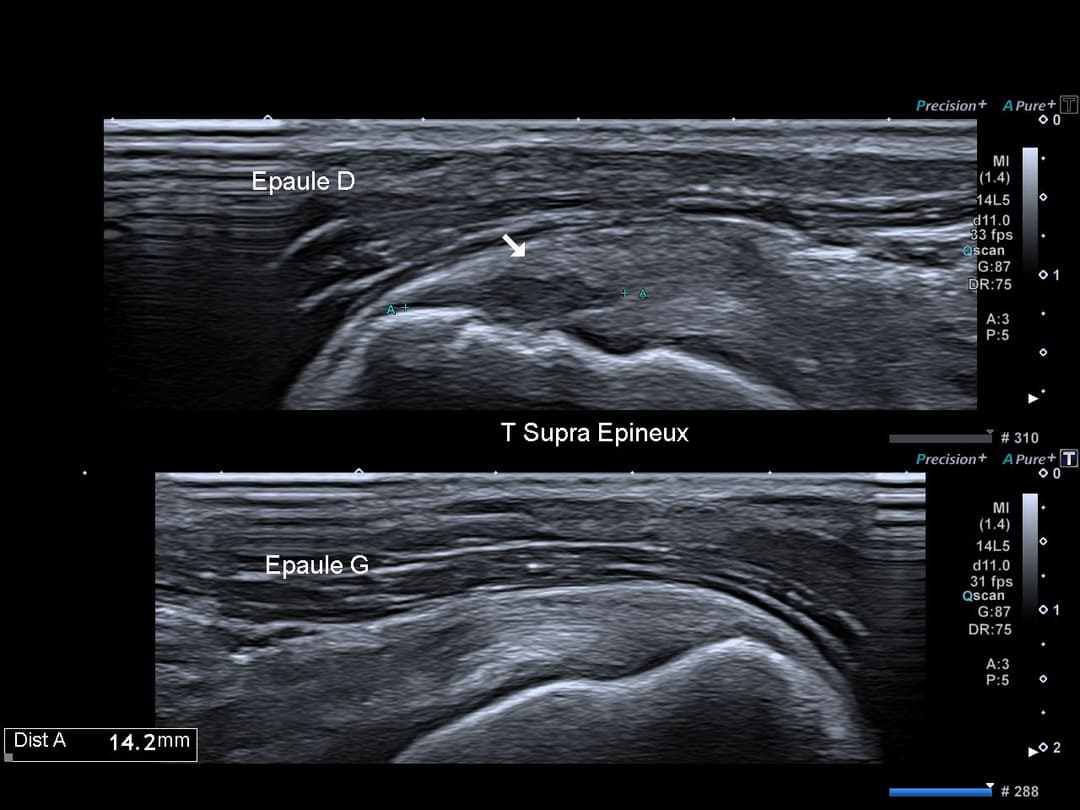

Comparatif du tendon supra épineux

Perte de l'architecture habituelle à double corde du tendon supra épineux, désorganisation hypoéchogène de la face superficielle (bursale) du tendon supra épineux traduisant une rupture partielle.

Rupture de la face bursale du tendon supra épineux avec conservation de sa face articulaire